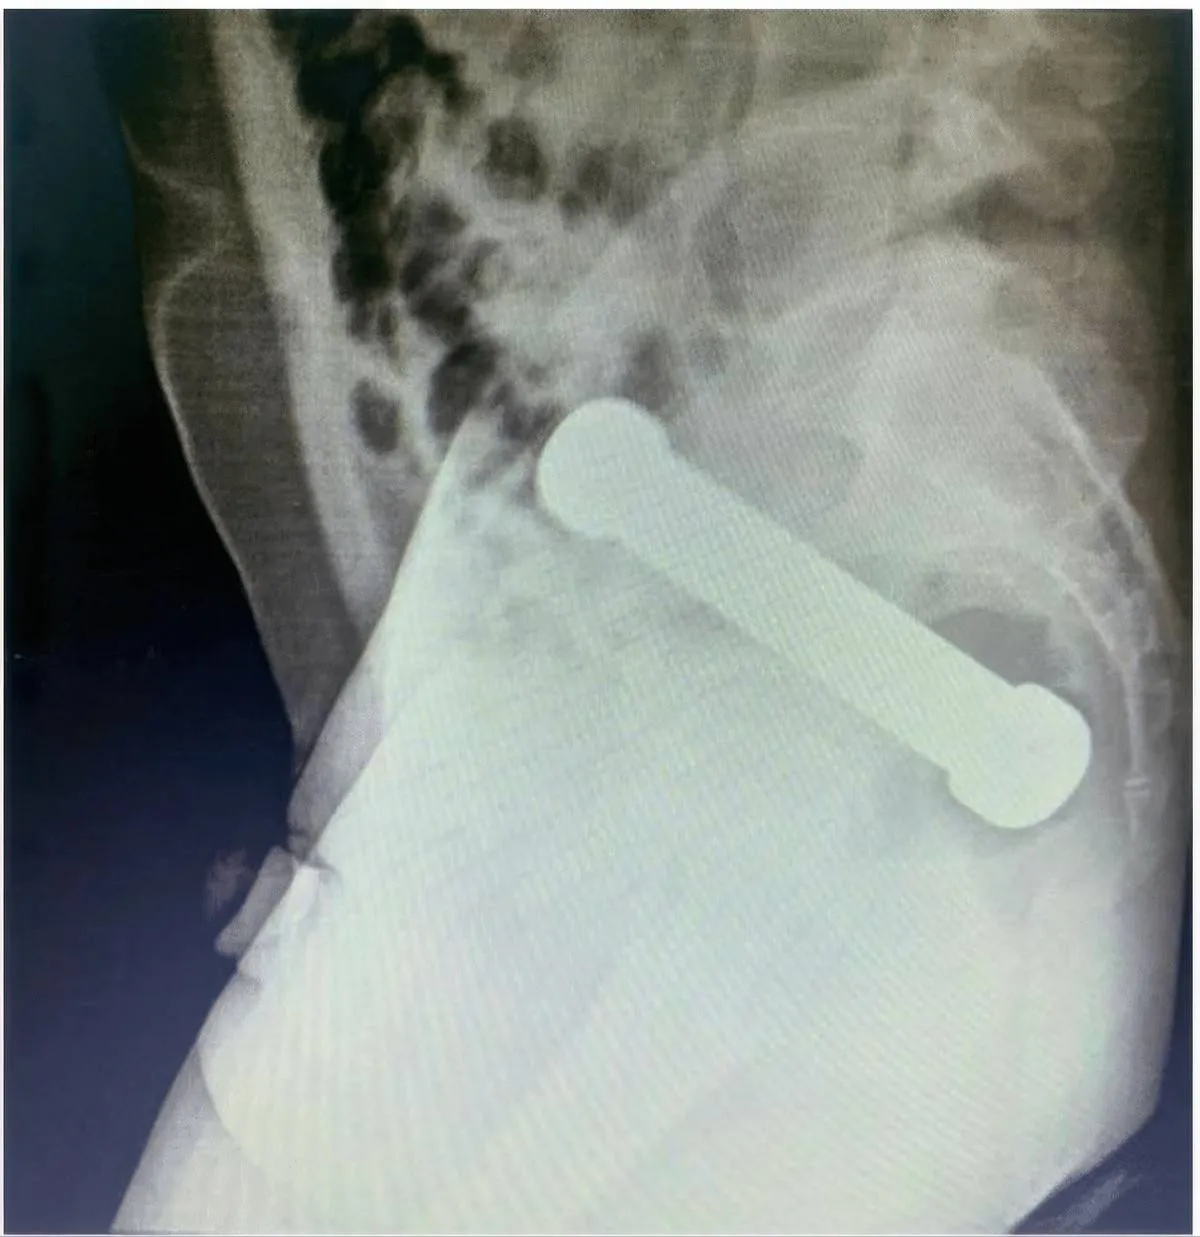

picture_vk_dumbell_brasil_02

Röntgenfoto van het bekken (zijaanzicht) waarop een vreemd voorwerp (halter/dumbbell) te zien is. (Foto: International Journal of Surgery Case Reports)